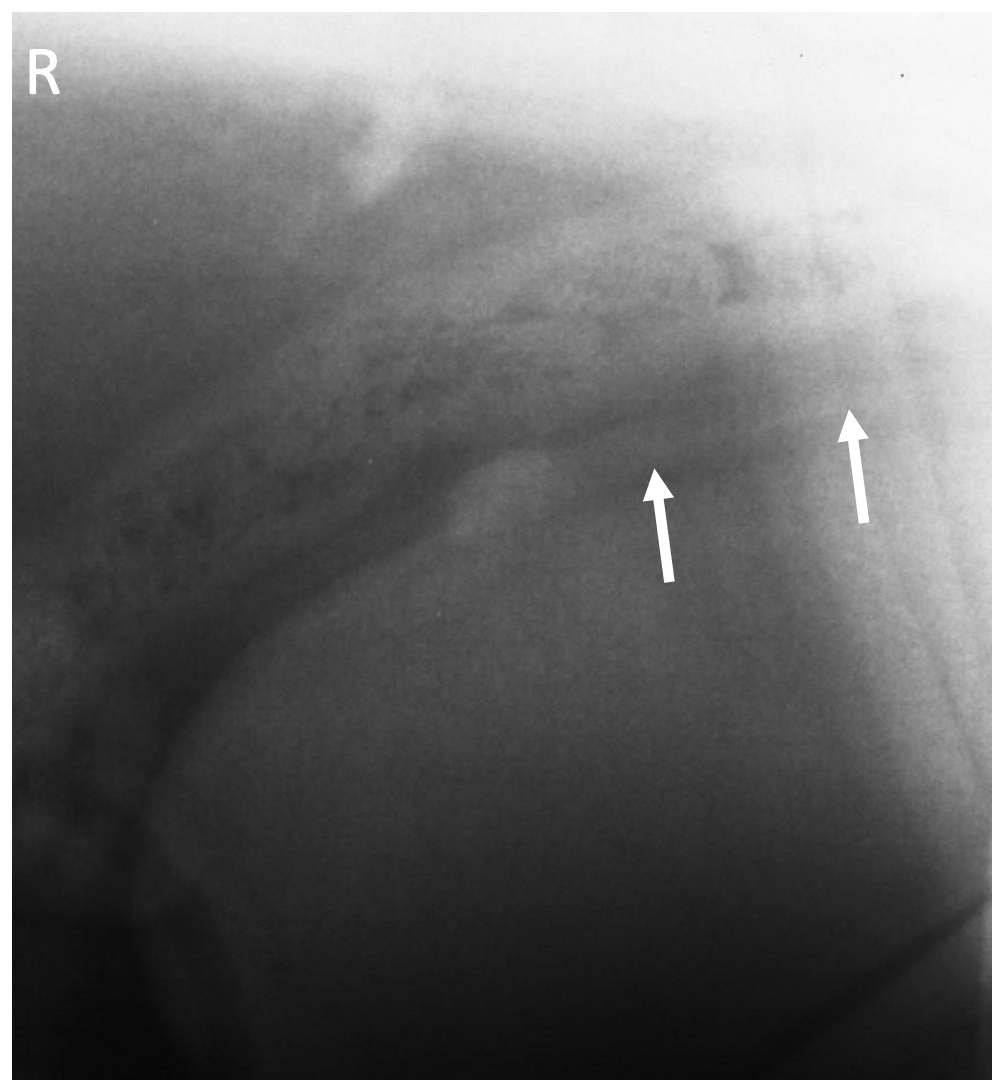

What is shown in this image?

lateral horizontal beam showing mineralized fetal skeleton in thorax and abdomen; displaced uterus from previous trauma